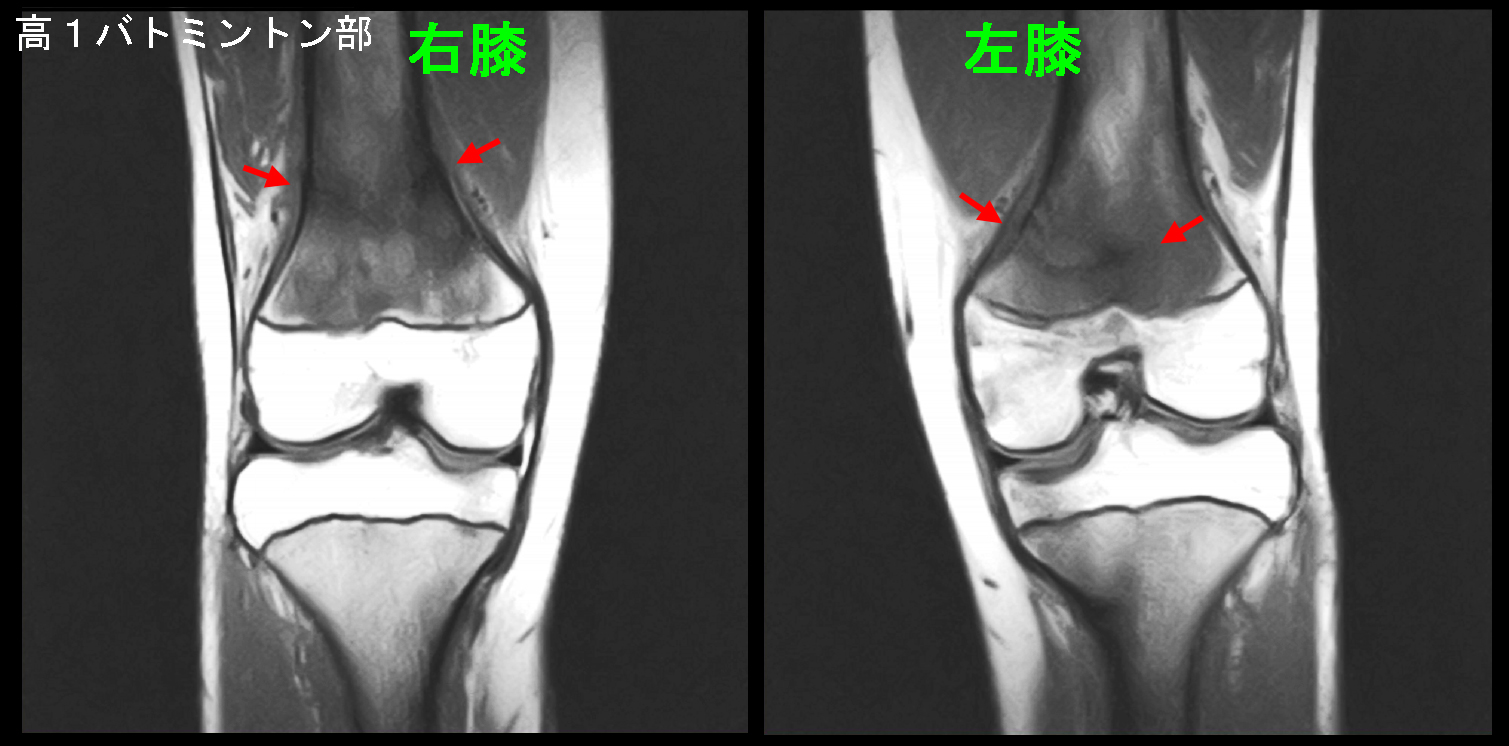

初診時(膝痛発症後4.5週後)のMRI画像です。

初診時MRI.jpg

このMRI検査条件では本来骨は白い色調となるはずですが、右大腿骨だけでなく左大腿骨も膝上で黒い色調となっています。これは骨が損傷している所見となります。赤矢印は骨折線となります。